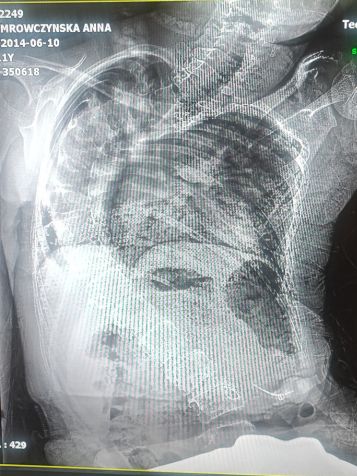

W 33 tygodniu ciąży podczas badania USG dowiedzieliśmy się, że nasze maleństwo ma powiększoną miedniczkę nerkową oraz prawą komorę mózgową. Lekarze po wnikliwych badaniach uspokoili nas, że takie powiększenia o niczym nie świadczą, że czasem tak jest, później mogą zniknąć. 10 czerwca 2014 r. przyszła na świat Ania. Łzy szczęścia płynęły nam po policzkach! Nasza kruszynka z cudownymi oczkami, czarnymi jak węgielki i bujną czupryną, była taka piękna! Ponownie wykonano komplet badań i stwierdzono, że nie ma powodów do niepokoju...

Ania według statystyk powinna być z nami zaledwie dwa lata… Dzięki ciągłej walce: rehabilitacji, terapii, suplementacji, odpowiednio dobranym sprzętom i gronie cudownych Aniołów, którzy nieustannie przy nas trwają, nasza Mróweczka niedługo skończy 10 lat. Choć staramy się robić wszystko, by Ania jak najmniej cierpiała, widzimy i jesteśmy świadomi tego, że choroba postępuje. Anusia bardzo źle widzi na jedno oko, ma słabe serduszko, a część jej płuc przestała funkcjonować. Prawe płuco jest już zdeformowane i bardzo utrudnia oddychanie. Musimy uważać na każdą infekcję, bo nawet najmniejszy kaszel może doprowadzić do tragedii. Wprowadziliśmy rehabilitację oddechową, która powtarzana kilka razy dziennie przynosi, minimalne ale jednak korzyści. Dodatkowo doszła skolioza, która powoduje ogromne cierpienie! Zniekształcenia klatki piersiowej może spowodować ucisk na narządy wewnętrzne, w szczególności płuca i serce, które i tak są bardzo słabe, co z kolei może być przyczyną niewydolności krążenia i układu oddechowego...